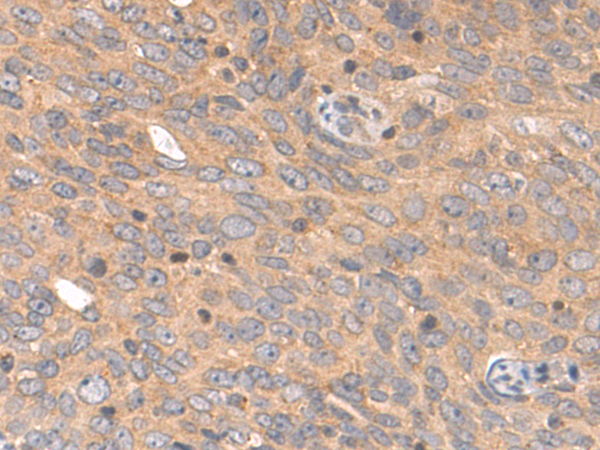

分类: 科研抗体货号: P07706别名: FHL5; UNC18B; Hunc18b; UNC18-2; pp10122; MUNC18-2应用: WB,IHC反应种属: Human, Mouse, Rat